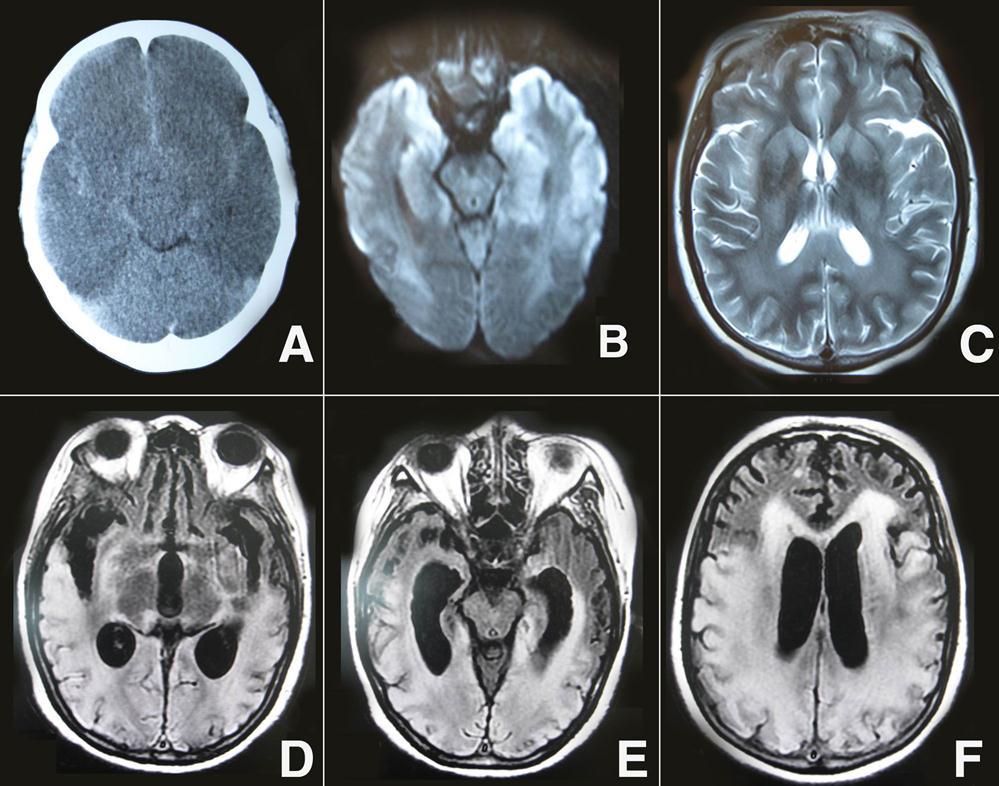

A 46-year-old woman was found in cardiorespiratory arrest after she had an out-of-hospital an suddenly drop atroke lasting about 27 min. She was successfully resuscitated and admitted to the intensive care unit.The etiopathogenesis of cardiac arrest was ventricular fibrillation for patient. On initial examination, her pupils were 2 mm in diameter and nonreactive to light, and there was unresponse to external stimulation, and the score on the Glasgow Coma Scale was 3(E1V1M1). On admition, initial head CT revealed no significant findings. On the three days after onset, a repeat noncontrast CT images showed a whole cerebral brain swelling, caudal transtentorial Herniation, and microhemorrhages in the intercerebral and subarachnoid (Figure 1A). Diffusion- weighted magnetic resonance imaging (DWI) performed on day 14, the patient showed extensive lesions of the bilateral middle, hippocampus and the gray matter of the frontal and temporal cortices (Figure 1 B). In addition, brain MRI T2-weighted imaging showed bilateral symmetric high signal intensity in the caudate, putamen, thalami, occipital, parietal cortices and subcortical white matter (Figure 1C). After 20 days, her neurological status was improved, the GCS scale was 8 (E4V1M3). she did not show any signs of conscious perception regarding the different types of stimulation, including pain. She had been in a vegetative state. On follow-up MRI 60 days later, Fluid-attenuation inversion recovery image (FLAIR) showed cortical, subcortical white matter, and periventricular white matter confluent hyperintense lesions in the bilateral temporal, parietal, and occipital regions, and enlarged ventricles (Figure 1D-F). After three months, she did not perform requested commands and displayed spastic palsy to a higher extent in the lower limbs. The GCS scale was 9 (E4V1M4), and she was declared a persistent vegetative state.

Figure 1.A) Brain CT showed a whole cerebral brain swelling, caudal transtentorial Herniation, and microhemorrhages in the intercerebral and subarachnoid; B) DWI showed extensive lesions of the bilateral middle, hippocampus and the gray matter of the frontal and temporal cortices; C) brain MRI T 2-weighted imaging showed bilateral symmetric high signal intensity in the caudate, putamen, thalami, occipital, parietal cortices and subcortical white matter; D-F) On follow-up MRI 60 days later, FLAIR showed cortical, subcortical white matter, and periventricular white matter confluent hyperintense lesions in the bilateral temporal, parietal, and occipital regions, and enlarged ventricles.

Post-Resuscitation Encephalopathy (PRE), is a relatively frequent condition. PRE is introduced as a term to describe the comatose state after CPR.1 The prognosis of CPR is different, depending on whether the brain damage is reversible or irreversible. Our patient was confirmed that early CT scan of CPR may not have abnormal changes, and upon to the 2-3 days later she had obvious diffuse edema and minor intercerebral hemorrhages. Therefore, the monitoring of the diffuse edema and mimic minor hemorrhages on brain CT is useful for an early diagnosis of PRE. However, most studies have confirmed that MRI is more useful for predicting prognosis than CT scan. On the day 14 after onset, DWI showed extensive lesions of the bilateral middle, hippocampus, caudate, putamen, thalami, occipital, parietal and the gray matter of the frontal and temporal cortices. Previous studies indicated that presence of a lesion pattern of multilobar, or diffuse, cortical involvement, termed as "extensive cortical lesion pattern", and associated with poor outcome. 2, 3 In fact, on the 20 days of onset, the patient'neurological status was improved, and her GCS scale was 8 (E4V1M3). Moreover, on follow-up MRI 60 days later, the hyperintense lesions in the bilateral frontal, thalami, and middle have been reversed,suggesting some cortical and subcortical cerebral lesions were reversible. However, periventricular white matter confluent hyperintense lesions in the bilateral temporal, parietal, and occipital regions have not been reversed, suggesting these hyperintense lesions were irreversible. An earlier study has showed that patients with bilateral basal ganglia, thalami, and/or substantia nigra lesions may survive in a persistent vegetative state (PVS).4 Current MRI-FLAIR found that patients with bilateral temporal, parietal, and occipital extensive lesions may also survive in a PVS.